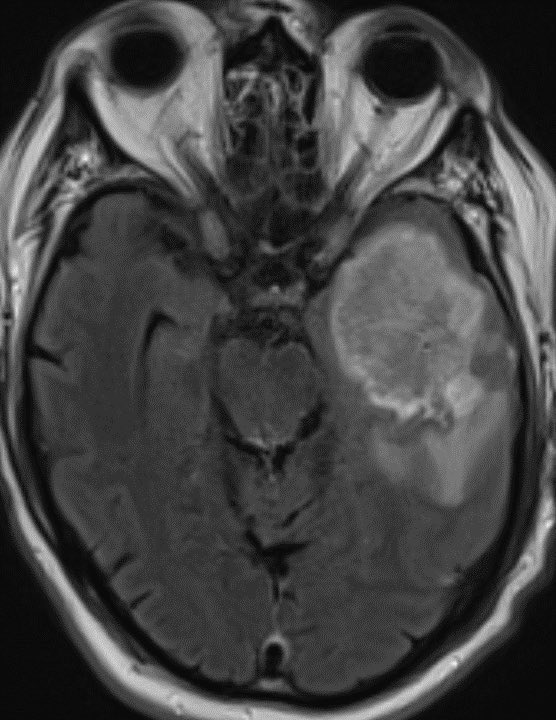

Glioblastoma is the most common variety of astrocytoma

The presence of necrosis is the characteristic feature of glioblastoma

Some correlates for high grade astrocytoma include necrosis, marked mass effect, restricted diffusion (often patchy, eccentric or nodular in glioblastoma), elevated CBV, enhancement, and older age

Important learning point: when dealing with glioblastoma, the neoplasm extent is not defined by the area of enhancement but rather by the entire area of T2/FLAIR abnormality. Microscopic infiltrating tumor clearly extends beyond the areas of enhancement. 🧠

When dealing with a known or presumed glioblastoma/high grade astrocytoma, I typically report the area of high T2/FLAIR signal surrounding the necrotic mass as “infiltrating tumor and/or vasogenic edema” knowing that there is a very high probability of microscopic spread

Radiation oncologists treat the entire area of abnormal signal (not just the enhancing portion) with the expectation of infiltrating tumor. Then they typically do a more focused port around the enhancing portion. 🧠